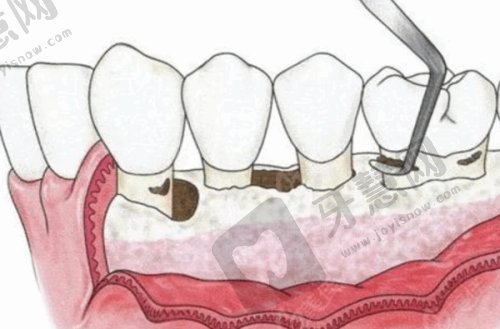

6. 激光牙周治疗:运用Er:YAG激光治疗牙周炎,无需切开牙龈即可清除牙结石,减少出血与术后反应;